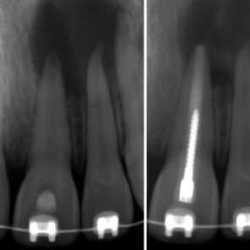

Inicio Especialidades Endodontia